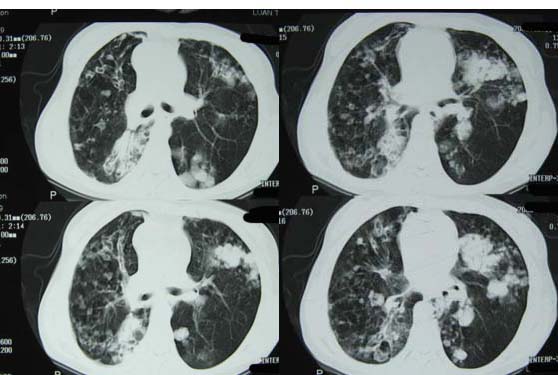

标题: CT8382:男,75,咳嗽,咳血有半年时间。 [打印本页]

标题: CT8382:男,75,咳嗽,咳血有半年时间。

右肺下叶弥漫性片状增高影 纤维组织增生   左肺上叶尖段大结节样增高影边界清楚 中叶下叶大片增高影(内可见钙化)

1.吸入性肺炎(真菌性)

2.干酪型肺炎

3.继发性肺结核?

考虑 双肺继发性肺结核

1双肺支气管扩张  2双肺多发块状影,考虑:转移瘤;3肝门区圆形软组织影,先考虑:转移淋巴结可能性大.

1.考虑双肺转移,建议增强ct及纤支镜;

2.双肺肺气肿,支扩伴少许感染;

3.双中上肺陈旧性病灶。

右上肺后段及左上肺舌段片状影,考虑双肺结核。

双肺弥漫性结节影,考虑双肺转移性肿瘤。